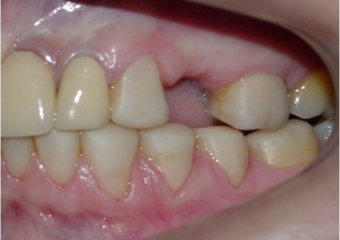

Imagem após extração do dente comprometido